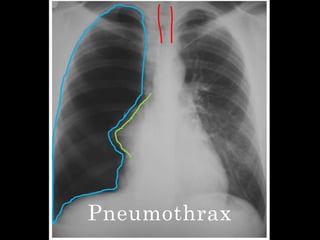

Pneumothrax

Pneumothorax

   Increased volume of the right hemithorax

with tracheal shift to the OPPOSITE side-

”PUSH” effect

   Hyperlucency on the right side

   Absence of lung markings

   Presence of margin of collapsed lung at the

hilum

   D/D:Unilateral emphysema

Pneumothorax  Increased volume of the right hemithorax with tracheal shift to the OPPOSITE side- ”PUSH” effect  Hyperlucency on the right side  Absence of lung markings  Presence of margin of collapsed lung at the hilum  D/D:Unilateral emphysema

• #25 Tracheal shift to the left-PUSH effect, increased volume of the right hemithoraxHyperlucency of right hemithorax + absence of lung markings + margin of collapsed lung(compression collapsed) = pneumothoraxTotal collapse=collapse like a cricket ball towards the hilum